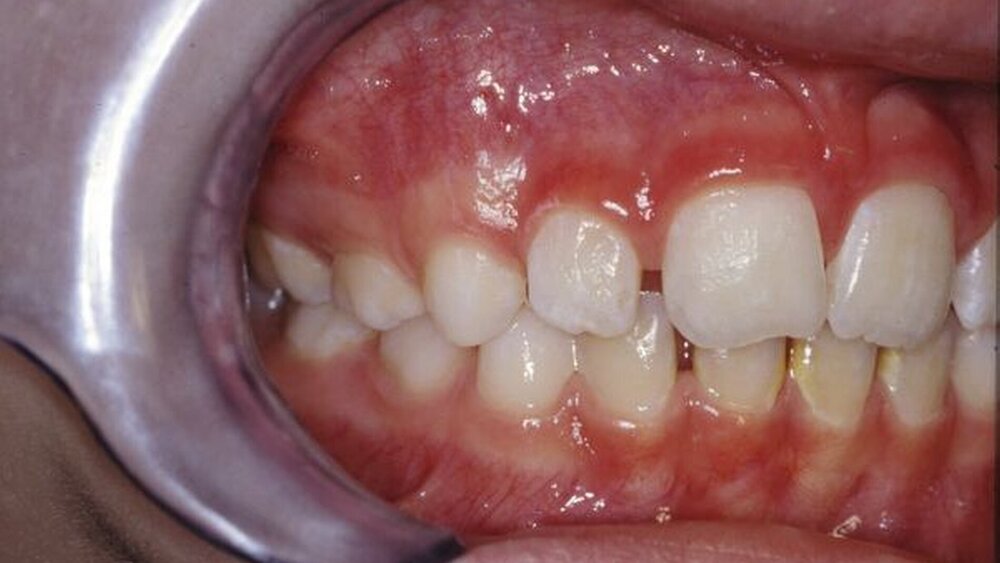

Der Kieferorthopäde Prof. Dr. Karl-Heinz Dannhauer, Leipzig, konnte mit seinem Beitrag überzeugend nachweisen, dass das Ernährungsverhalten im frühen Kindesalter maßgeblichen Einfluss auf die Gebissentwicklung und damit aber auch auf die Gesundheit im späteren Alter hat. Er ging auf die physiologischen und pathologischen Veränderungen der Schluckmuster unter dem Aspekt, in welcher Weise das Nahrungsangebot erfolgt (Stillen versus Flasche, feste Nahrung, Trinken aus der Tasse und mehr), ein.

Neben den Fütter- und Essverhaltensweisen, die sich direkt auf die Zahn- und Gebissentwicklung auswirken, ging es dann in einem weiteren Beitrag von Mary Ann Bolten, Wiesbaden, sie ist Speech Pathologistin und Mundfunktionstherapeutin, um Ursachen von Habits, die im frühen Kindesalter ihren Anfang haben und eng im Zusammenhang mit der Bedürfnisbefriedigung des Kindes stehen. So können orofaziale Funktionen beziehungsweise Dysfunktionen (Nasenatmung, Schluckstörungen, Mobilitätsbeeinträchtigungen der Zunge, Lutschgewohnheiten) die skelettale Entwicklung beeinflussen.

Therapeutische Konzepte, die sich – wie die Myofunktionelle Therapie (MFT) – diesen Dyskinesien widmen, können hierbei sehr erfolgreich die Mund- und Kaumuskulatur beeinflussen und so zum Beispiel die physiologische Atmung durch Training des Lippenschlusses wiederherstellen und damit eine kieferorthopädische Behandlung sinnvoll begleiten und unterstützen. In einem Fallbericht konnte Sabine Fuhlbrück, Myofunktionstherapeutin sowie kost®-Therapeutin, dieses eindrucksvoll belegen. Die körperorientierte Sprachtherapie nach Codoni stellt darüber hinaus die Zusammenhänge zwischen Form und Funktion, bezogen auf den ganzen Körper dar. Bei den meisten sprachbehinderten Kindern liegen sowohl Störungen des Gleichgewichts der oralen Muskelfunktionen als auch Dysbalancen in anderen Körperbereichen vor. Nur wenn diese unter Einbeziehung der entsprechenden medizinischen Fachgebiete korrigiert wurden, kann darauf aufbauend die Myofunktionelle Therapie einen wirksamen Beitrag für die Sprach- und Sprechent wicklung leisten. Mit zahlreichen Vorher-Nachher- Bildern von entsprechend therapierten Patienten bewies Ulrike Hörstel aus Günzburg, MF-Therapeutin, Logopädin, kost®-Therapeutin, den Erfolg dieses Konzepts. Cathrin Wegner, Hagenow, Logopädin, NLP-Trainerin, kost®-Therapeutin, rundete die Palette der Vorstellung von Therapiekonzepten oraler Habits mit der Kasuistik über die Lutschentwöhnung durch neurolinguistische Programmierung (NLP) bei einem elfjährigen Patienten ab. Auch hier gelang es der geschulten Therapeutin innerhalb kurzer Zeit, dem Wunsch des heranwachsenden Jungen zu entsprechen, indem er durch die Verbesserung des eigenen Wohlbefindens auch seine Lebensqualität steigern und eigenverantwortlich Entscheidungen treffen konnte.